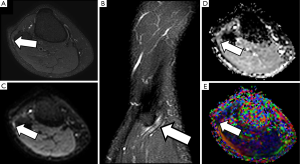

The sciatic nerve is the major PN in the body, both for its length and its width. Clinical manifestations of sciatic nerve are common, and are challenging to study with MRI due to its length. Sciatic nerve entrapment usually occurs at a pelvic level, the so-called piriformis syndrome, due to a mass compression, trauma or a compression neuropathy (68,69). According to some authors, the existence of a piriformis hypertrophy, as may occur in runners, or accessory muscle can condition compression on the sciatic nerve and justify the symptoms (70,71). Morphological MRI is able to determine the anatomy of the piriformis muscle and its relation with the sciatic nerve, bur may not always show enough accuracy for detecting changes at the sciatic nerve that justify the symptoms. However, DWN allows multiplanar reconstructions that facilitate the qualitative assessment of the nerve in almost its entire length, detecting differences in signal intensity of the sciatic nerve in comparison to the contralateral, healthy one (Figure 13). Furthermore, at the point of nerve compression, ADC shows higher values than in the rest of the nerve, presumably due to the coexistence of edema (40,72). 3D neurographic reconstructions from DTN data may help in the assessment of the relationship between sciatic nerve and piriformis muscle and its several variants that may help clinicians to establish a most certain diagnosis of this underdiagnosed entity (73) (Figure 14).

Distal sciatic neuropathy with peroneal nerve compression as it crosses around the knee by extrinsic lesions or the insertion of flexor muscles is not uncommon, and functional MRI neurography may help to clarify the potential involvement of this nerve and its correlation with electrophysiological studies and clinical symptoms (Figure 15).